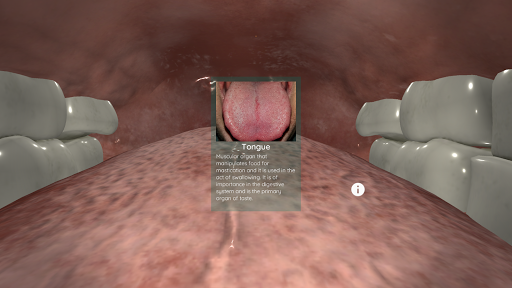

Anatomyou VR est une application mobile éducative qui présente l'anatomie humaine à l'utilisateur d'une manière immersive.

En utilisant la réalité virtuelle, vous serez capable de naviguer le long des structures anatomiques, devenant une partie de l'anatomie humaine: circulatoire, respiratoire, digestive, urinaire, lacrymale et système reproducteur féminin.

Ceci est une version récemment rénovée d'Anatomyou VR. Les fonctionnalités incluent: - Anatomie humaine plus réaliste, améliorant les modèles et les textures. - Meilleure interaction de l'utilisateur en mode VR et en mode plein écran. - Des menus et des images entièrement rénovés permettent une navigation intuitive. - Contenu clinique supplémentaire validé par nos experts. - Les utilisateurs précédents doivent accepter certaines autorisations (GoogleVR SDK). Nous avons mis beaucoup d'efforts dans cette mise à jour, j'espère que vous l'apprécierez!